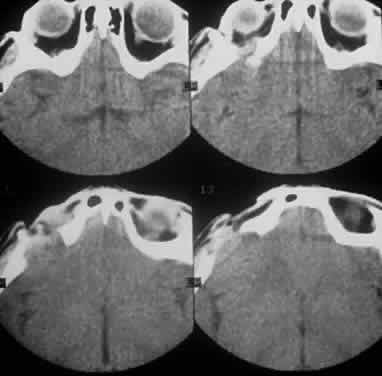

Computed tomography (CT) accurately demonstrates the molding of the mass to orbital structures, such as the globe and orbital bones, without bony erosion except in large cell lymphoma (Fig. 7). CT is used to localize the lesion, which tends to be unilateral and in both the intraconal and extraconal spaces. Lesions limited to the conjunctiva tend to be more benign with a better long-term prognosis, whereas those that extend into the orbit tend to be more malignant. Conjunctival lesions remain localized in 90% of cases, whereas orbital and lid lesions have a higher rate of systemic extranodal involvement.63 Lymphoid lesions of the lacrimal gland appear as a diffuse vertical expansion of the gland, which mold to both the globe and orbital bone without producing a bony fossa or erosion64 (Fig. 8). If the lesion extends beyond the orbital rim, the palpebral lobe of the gland is involved, and posterior or orbital lobe involvement appears as a straight line against orbital fat. Pleomorphic adenoma, on the other hand, appears as an oval, globular lesion with, in 80% of cases, adjacent bone changes caused by the firmer stroma of the tumor. Because epithelial tumors usually arise in the orbital lobe, extension beyond the orbital rim is not a feature.65 CT scan cannot distinguish between inflammatory and lymphoid lesions, because both lesions are homogeneous and enhance with intravenous contrast, and at biopsy, orbital lymphoid lesions are pink with a friable texture caused by the absence of stroma.66–68 The subtype and malignancy of the lesion can only be determined morphologically. The following subtypes of B-cell nonHodgkin's malignant lymphoma—extranodal B-cell marginal zone lymphoma, follicle center cell lymphoma, small lymphocytic lymphoma, lymphoplasmacytoid lymphoma, mantle cell lymphoma, large cell lymphoma, and Burkitt's lymphoma—are discussed in the approximate order of frequency with which they occur in the orbit.

Fig. 7. A CT scan, axial view, of the patient in Figure 6 showing molding of the lymphoma to adjacent extraocular muscle, globe, and medial orbital wall.